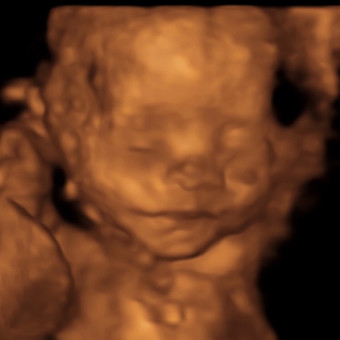

From my tiny heart to yours, thank you for helping my parents get ready for me. I’m already so loved, and I can’t wait to be cuddled by you.💙. We won’t know what works best for baby boy until he’s here so please help us with including gift receipts. Thank you!